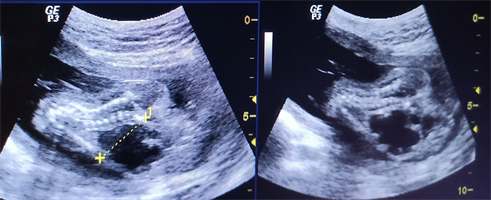

It was a young 19-year-old woman received as part of the prenatal consultation, first ultrasound. The patient had no medical and surgical history. The examination was carried out at the radiology department of the reference health center of commune III of the district of Bamako in Mali using a GE (General Electric) type device (General Electric) brand LOGIQ P3 with color Doppler equipped with 3 multi-frequency probes ( convex, endovaginal and barrette) and put into service in 2008. Obstetric ultrasound performed with the convex probe (2-5 MHz) found: a defect in the closing of the anterior abdominal wall with herniation of the viscera floating freely in the liquid amniotic (liver, gallbladder, intestines and stomach) whose neck was 31 mm in diameter. This is associated with moderate dilation of the right lateral ventricle at brain level (Figure 1).

Figure 1. Mode B ultrasound showing the viscera floating in the amniotic fluid without membrane ((A) yellow arrow) and the dilation of the right lateral ventricle ((B) yellow arrow).